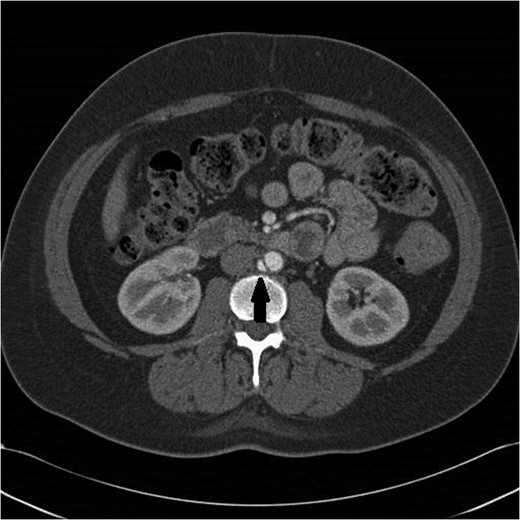

A 47-year-old woman with a history of hypertension and smoking was involved in a high-speed motor vehicle accident and presented to the emergency department with back pain. Computed tomographic (CT) scans were obtained of her abdomen and pelvis. On a single image from the abdominal scan, what appeared to be either an intimal flap or a small amount of contrast extravasation outside of the infrarenal aorta could be seen. Her care providers had differing opinions as to what was being seen on the image. Since the abnormality was only seen on a single image, the exact etiology could not be delineated (Fig. 1). The patient was observed in the hospital overnight, had minimal complaints the next day, and was discharged on aspirin.

Initial CT scan shows enhancing vascular abnormality on the right side of the aorta, shown by the black arrow.